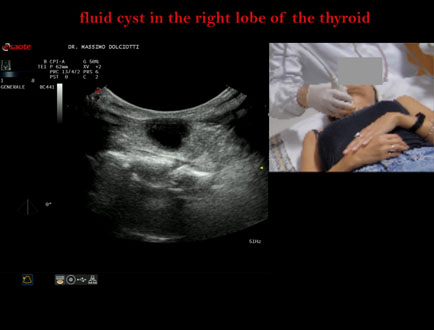

Data inserimento: 05/11/2025

Ecografia del: 27/10/2025

Strumento: Esaote MyLab Eight

Sonda: Lineare Multifrequenza 3-13 MHz e Volumetrica Multifrequenza 1-8 MHz

Età Paziente: F 44 anni

Motivazione dell'esame: rapida comparsa di tumefazione in sede cervicale anteriore, lievemente dolente alla palpazione.

Commento all'esame: le immagini ed il video documentano al terzo medio del lobo destro della tiroide, formazione anecogena, a margini regolari, senza segni di vascolarizzazione, delle dimensioni di 16,9 x 19 mm, da ricondurre a cisti liquida.

Conclusioni: cisti liquida al lobo destro della tiroide (fluid cyst in the right lobe of the thyroid).

Presentazione: Dr. Massimo Dolciotti - Ancona

Elaborazione digitale: Andrea Dini - Ancona